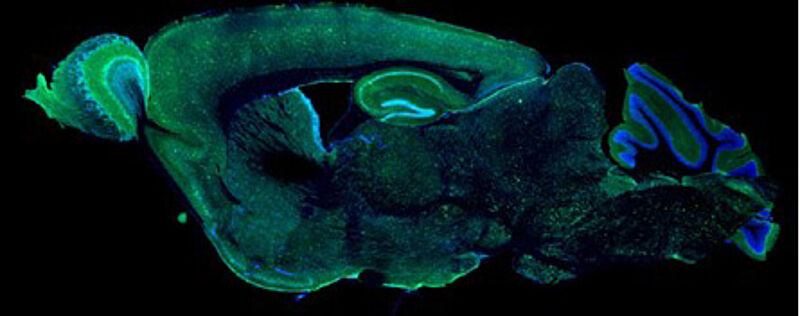

Il n’existe à ce jour, aucun traitement curatif pour la Sclérose Latérale Amyotrophique et les dégénérescences lobaire fronto-temporales, des pathologies neurodégénératives progressives rares ayant des caractéristiques communes mais dont l’étiopathogénie est complexe et pas entièrement comprise. 97% des patients atteints de SLA et 45% des DLFT présentent une accumulation/agrégation cytoplasmique anormale de la protéine TDP-43 (transactive response DNA-binding protein 43) principalement dans les neurones mais également les cellules gliales, conduisant aux symptômes moteurs et cognitifs observés dans ces deux pathologies. Néanmoins, la plupart des modèles animaux de pathologies TDP-43 existants, sont basés sur des mutations génétiques et ne reflètent donc pas l’ensemble des cas sporadiques. Notre projet vise  à développer un nouveau modèle sporadique TDP-43 afin de mieux comprendre les mécanismes physiopathologiques impliqués et tester deux approches thérapeutiques que nous développons dans le centre Lille Neuroscience & Cognition dans la SLA et des DLFT: le lysat plaquettaire et un antagoniste des récepteurs adénosinergiques A2A.